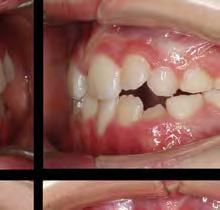

–MARPE, una alternativa a la disyunción en el paciente adulto, por el Dr. Enrique Solano y cols. [88]